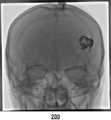

도 3c는 본 발명의 일실시예에 따라 획득된 조영제가 정맥을 통과 할 때 제2영상의 예시도면이다.

3C is an exemplary illustration of a second image when the contrast agent acquired in accordance with one embodiment of the present invention passes through a vein.

예를 들어, 상기 영상이 조영제를 주사하여 촬영한 혈류영상(즉, 혈관조영영상)인 경우, 시계열데이터는 특정시간 간격으로 획득된 제2영상(200) 프레임을 통해 측정된, 각 지점의 시간별 조영제에 의해 증강된 신호의 측정량 데이터일 수 있다. 혈관조영영상은 각 프레임마다 조영제에 의해 특정 영역이 증강된 2차원 영상을 포함하고 있다. 즉, 조영제를 주사하기 전에는, 도 3a에서와 같이, 조영 증강된 혈관영역이 존재하지 않다가, 동맥으로 조영제가 주사되면, 도 3b에서와 같이, 동맥영역이 밝아졌다가 시간이 흐름에 따라 조영제가 혈류와 함께 정맥쪽으로 이동하면서, 도 3c에서와 같이 정맥영역이 밝아지게 된다. 컴퓨터는 각 프레임 내에서 사용자가 선택한 특정한 지점(즉, 특정한 좌표)에 대응하는 밝기값을 추출한다. 상기 컴퓨터는 상기 추출된 밝기값을 각 프레임이 획득된 시간 순서에 따라 시계열데이터로 생성할 수 있다. 예를 들어, 혈관조영영상의 총 프레임 수가 n개인 경우, 1*N의 행렬을 생성하여 추출한 밝기 값을 순서대로 상기 행렬 내에 입력할 수 있다. 상기 컴퓨터는 상기 행렬 데이터를 바탕으로 그래프를 생성(plot)하는 등의 시계열 분석을 수행할 수 있다.For example, when the image is a blood flow image (i.e., an angiogram image) taken by scanning the contrast agent, the time series data may include time-series data measured through a

또한, 상기 시계열데이터(300) 제공단계(S400)는, 상기 사용자로부터 선택된 특정지점에 대한 상기 조영제 도착시점 이후 특정시점의 제1 또는 제2영상(200)을 표시하는 단계;를 포함할 수 있다. 도 3a 내지 도 3c에 도시된 바와 같이, 동맥으로 조영제를 주입한 후 통과되는 혈관의 위치에 따라 조영증강에 의해 강조되는 부분이 달라지게 된다. 의료진이 혈관 검사 시 혈관의 상태를 시각적으로 더 잘 파악하기 위해서는, 컴퓨터가 사용자로부터 선택된 특정지점을 많은 양의 조영제가 통과하여 선명하게 인식될 수 있는 제1 또는 제2영상(200)의 프레임을 화면에 표시해줄 필요가 있다. 따라서 컴퓨터는 시계열데이터(300)를 바탕으로 선택된 특정지점을 통과하는 조영제 양이 특정기준 이상인 프레임을 추출하여 표시하도록 할 수 있다.The step of providing the